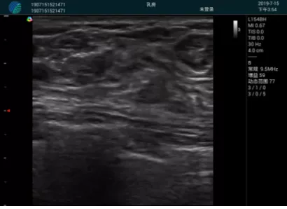

清晰顯示腺體內(nèi)低回聲快影,邊界清晰,包膜較光滑